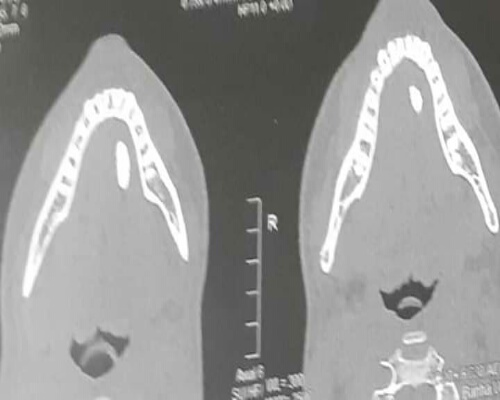

وقد تم ذلك بعد إجراء الفحوصات السريرية وعمل أشعة تلفزيونية ومقطعية لتحديد حجم وموقع الحصوة تفاديا لقرار استئصال كامل الغدة.